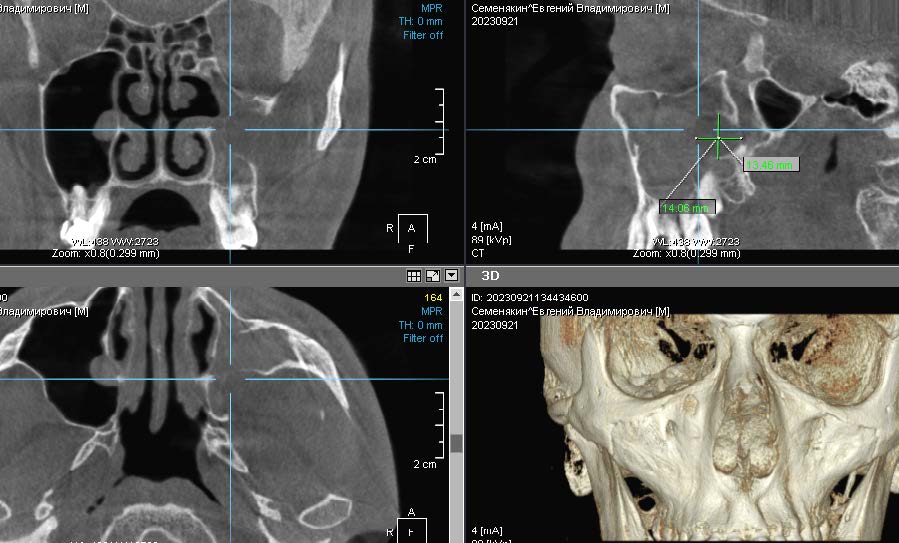

Возможности реформатора КЛКТ позволили визуализировать максимальное количество сечений ВЧП и окружающих ее структур для дифференциальной диагностики и последующего успеха оперативного вмешательства (рис. 5).

Рис. 5. Пациентка Э., предоперационное КЛКТ, вид ВЧП слева